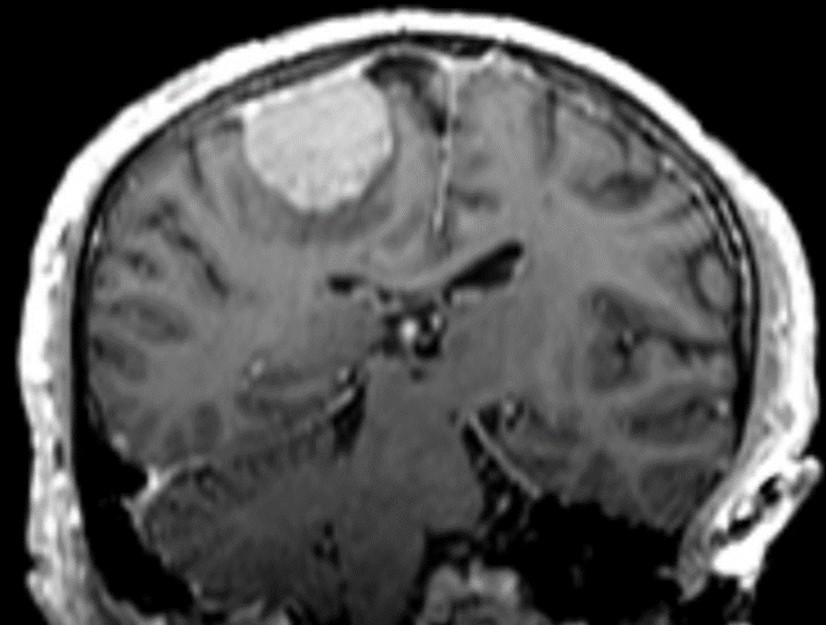

Treatment planning for LINAC-based radiosurgery has been performed by ERGO ++ (CMS, Elekta, UK) radiosurgery planning system. Optimal target coverage and normal tissue sparing has been achieved by using a single 360-degree arc, double 360-degree arcs, or five 180-degree arcs in radiosurgery planning. Synergy (Elekta, UK) LINAC available at our department has been used in delivery of treatment. Delineation of the target volume on planning CT and MR images has been optimized by selecting the appropriate windows and levels for radiosurgery planning. Sagittal and coronal images have been used in addition to the axial planning CT images to achieve accurate contouring of target volume and critical structures. Arc Modulation Optimization Algorithm (AMOA) has been utilized for optimization of target volume coverage and critical organ sparing. Figure 1 shows coronal CT image of a patient with atypical meningioma, and Figure 2 shows the corresponding coronal MR image of the same patient with atypical meningioma.

Figure 1.Coronal CT image of a patient with atypical meningioma

Coronal CT image of a patient with atypical meningioma